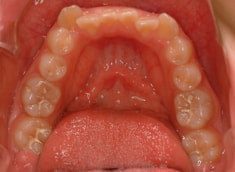

治療開始から5ヶ月後